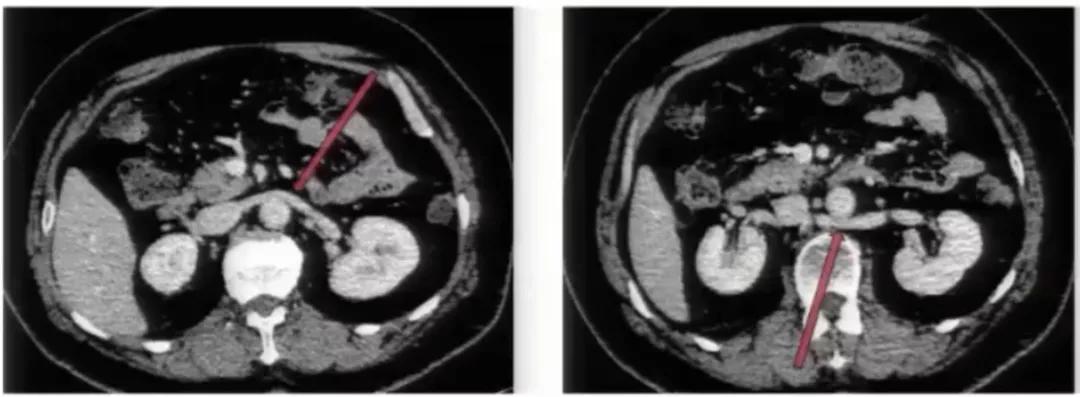

图11:腹主动脉两侧均有下腔静脉影,左侧下腔静脉向上与左肾静脉汇合后,在腹主动脉前方绕行,移行为右侧下腔静脉